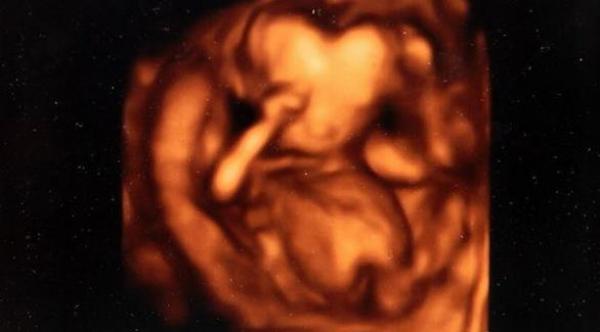

أصابت الأم بيفرلي وينتر صدمة بالغة عندما خضعت لفحوصات تقليدية لمعرفة نوع الجنين، ففوجئت هي وزوجها بجمجمة جنينها الذي يأخذ شكل قلب، بحسب موقع ميرور البريطاني.

وعندما شعر الأطباء بارتباك وذعر الزوجين، قاموا بطمأنتهما بأن طفلهما لا يزال في مرحلة التكوين، وأنه سيستعيد شكل الرأس الطبيعية مع اكتمال أسابيع الحمل، ما هدأ من روعهما، كونهما زوجين حديثي الزواج ولم يسبق لهما أن شاهدا حالة كهذه.

وبالفعل صدق الأطباء، وباكتمال نمو الجنين وبنهاية شهور الحمل وضعت بيفرلي طفلها الذي أسمياه "لوغان" في سبتمبر (أيلول) الماضي برأس طبيعية، سعادة، واحتفظا بصور "السونار" في ألبوم صور حتى يتسنى لطفلهما رؤيتها عند الكبر.